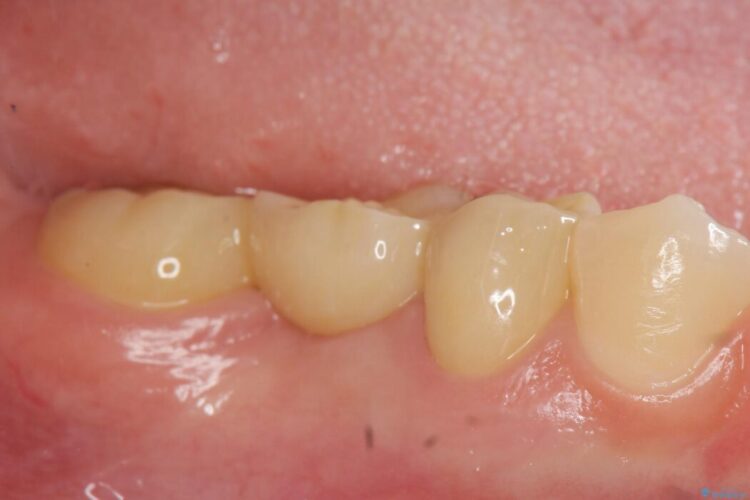

欠損した部分が補綴され、普通に噛めるようになったと喜んでいただけました。

本症例では、健康な歯を可及的に守るため神経の処置を避けた上で部分矯正を併用して行うことにより、安全に補綴治療(ブリッジ)ができました。